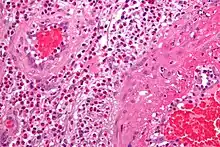

- The definite diagnosis of vasculitis is established after a biopsy of involved organ or tissue, such as skin, sinuses, lung, nerve, brain, and kidney. The biopsy elucidates the pattern of blood vessel inflammation.

- Some types of vasculitis display leukocytoclasis, which is vascular damage caused by nuclear debris from infiltrating neutrophils.[12] It typically presents as palpable purpura.[12] Conditions with leucocytoclasis mainly include hypersensitivity vasculitis (also called leukocytoclastic vasculitis) and cutaneous small-vessel vasculitis (also called cutaneous leukocytoclastic angiitis).